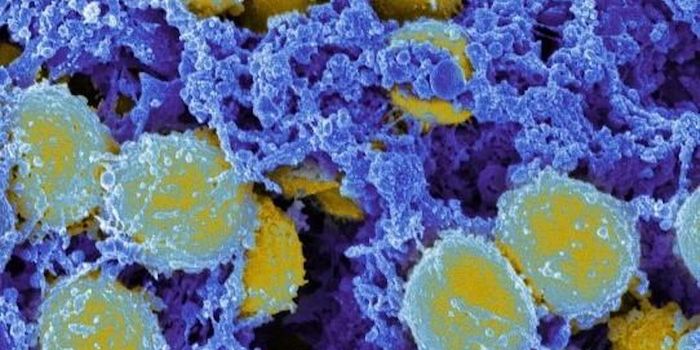

AUG 24, 2020ImmunologyOnce in the body, HIV tracks down T cells that bear the CD4 receptor. It attaches to these immune cells, fusing itself w ...